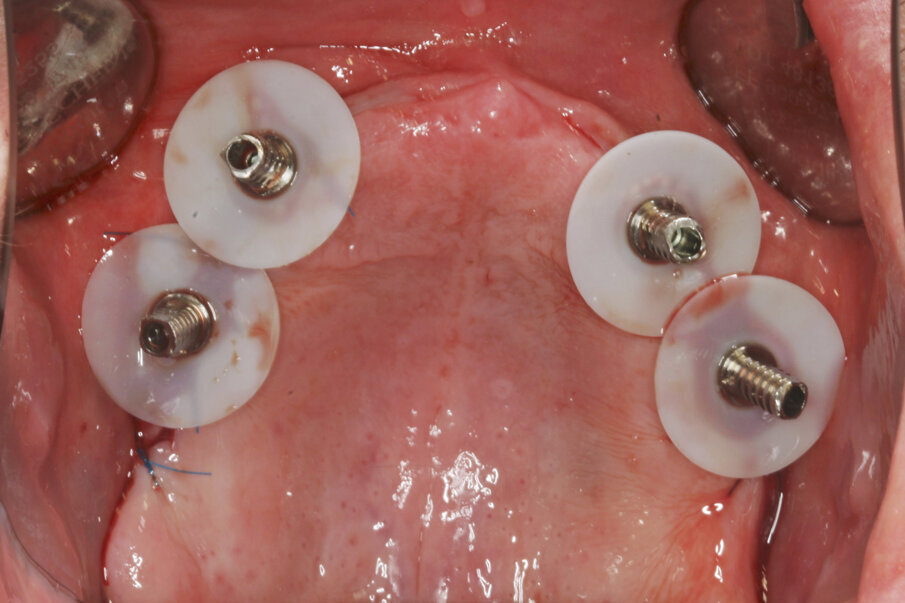

Prior to surgery, intra-oral scans of the edentulous upper jaw and dentate lower jaw were performed. The existing denture was used first as a surgical guide and then as a provisional prosthesis, after removing the palate (Fig. 4). Immediately after implant placement (Figs. 5–10), abutment position was registered with an intra-oral scan (Fig. 11). The provisional prosthesis was prepared fromthe existing denture (Figs. 12 & 13) and then the Atlantis BridgeBase was designed (Fig. 14).

Fig. 7: Multibase abutments inserted for immediate loading.

Fig. 8: The abutments were torqued to 25 Ncm.

Fig. 9: Temporary cylinders prepared with SynCone silicone sleeves (Dentsply Sirona) for intra-oral gluing.

Fig. 10: Intra-oral gluing of the temporary cylinders to the existing denture.

Fig. 11: Intra-oral scan of the abutment position, antagonists, provisional prosthesis and jaw relation for the manufacturing of the definitive prosthesis.